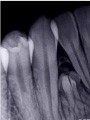

歯の硬組織の異常増殖を示す病変で組織奇形に属します。

小さな歯牙形態を呈する集合性歯牙腫と歯を構成する組織の異常形成による複雑性歯牙腫があります。